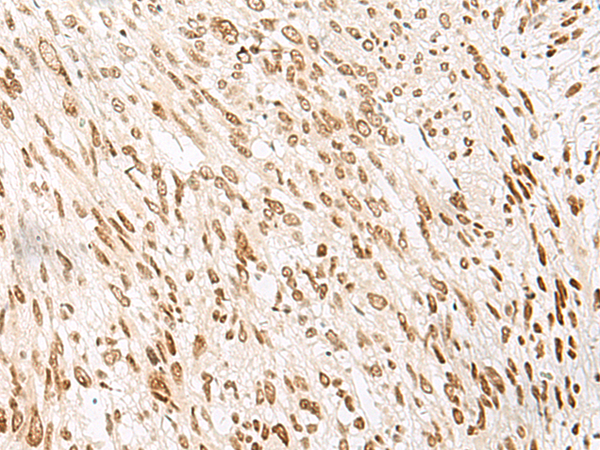

IHC positive control: |

Human breast cancer |

IHC Recommend dilution: |

10-50 |